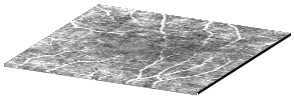

Optical coherence tomography angiography (OCTA) shows its great importance in imaging microvascular networks by providing accurate 3D imaging of blood vessels, but it relies upon specialized sensors and expensive devices. For this reason, previous works show the potential to translate the readily available 3D Optical Coherence Tomography (OCT) images into 3D OCTA images. However, existing OCTA translation methods directly learn the mapping from the OCT domain to the OCTA domain in continuous and infinite space with guidance from only a single view, i.e., the OCTA project map, resulting in suboptimal results. To this end, we propose the multi-view Tri-alignment framework for OCT to OCTA 3D image translation in discrete and finite space, named MuTri. In the first stage, we pre-train two vector-quantized variational auto-encoder (VQ- VAE) by reconstructing 3D OCT and 3D OCTA data, providing semantic prior for subsequent multi-view guidances. In the second stage, our multi-view tri-alignment facilitates another VQVAE model to learn the mapping from the OCT domain to the OCTA domain in discrete and finite space. Specifically, a contrastive-inspired semantic alignment is proposed to maximize the mutual information with the pre-trained models from OCT and OCTA views, to facilitate codebook learning. Meanwhile, a vessel structure alignment is proposed to minimize the structure discrepancy with the pre-trained models from the OCTA project map view, benefiting from learning the detailed vessel structure information. We also collect the first large-scale dataset, namely, OCTA2024, which contains a pair of OCT and OCTA volumes from 846 subjects.